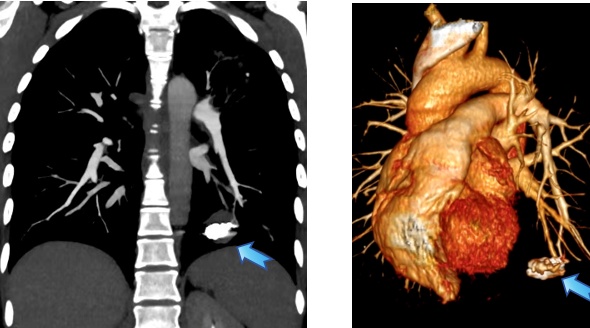

术后CTA复查:动脉瘤得到了精确且完全栓塞

术后第二天肺动脉CTA复查显示:动脉瘤被完全“封堵”,局部血流切断。王女士恢复平稳,未再出现咯血,随后顺利出院。她感慨道,感觉自己全好了!